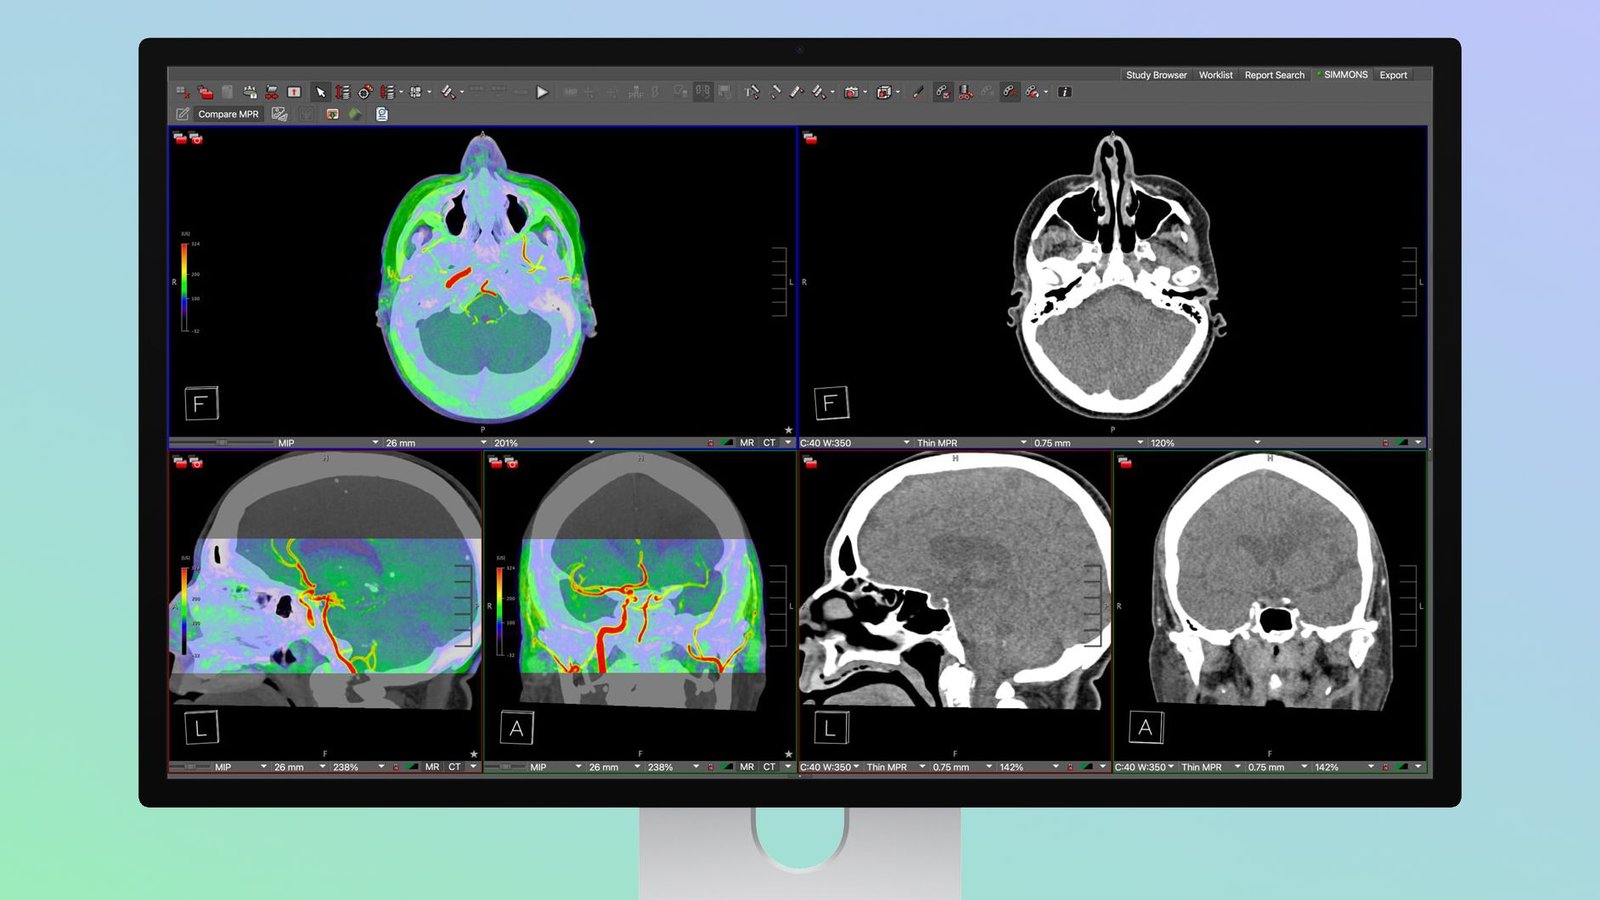

Studio Display XDR admite ajustes preestablecidos de imágenes médicas DICOM y un calibrador de imágenes médicas para que pueda usarse para radiología de diagnóstico. Los radiólogos podrán ver imágenes directamente en Studio Display XDR sin la necesidad de utilizar una pantalla de imágenes médicas de propósito único.

Existe una opción de cambio de modo de visualización para pasar de un modo de visualización estándar a un modo de visualización de radiología. El precio del Studio Display XDR comienza en $ 3299 y es más asequible que muchos monitores de imágenes médicas especializados.